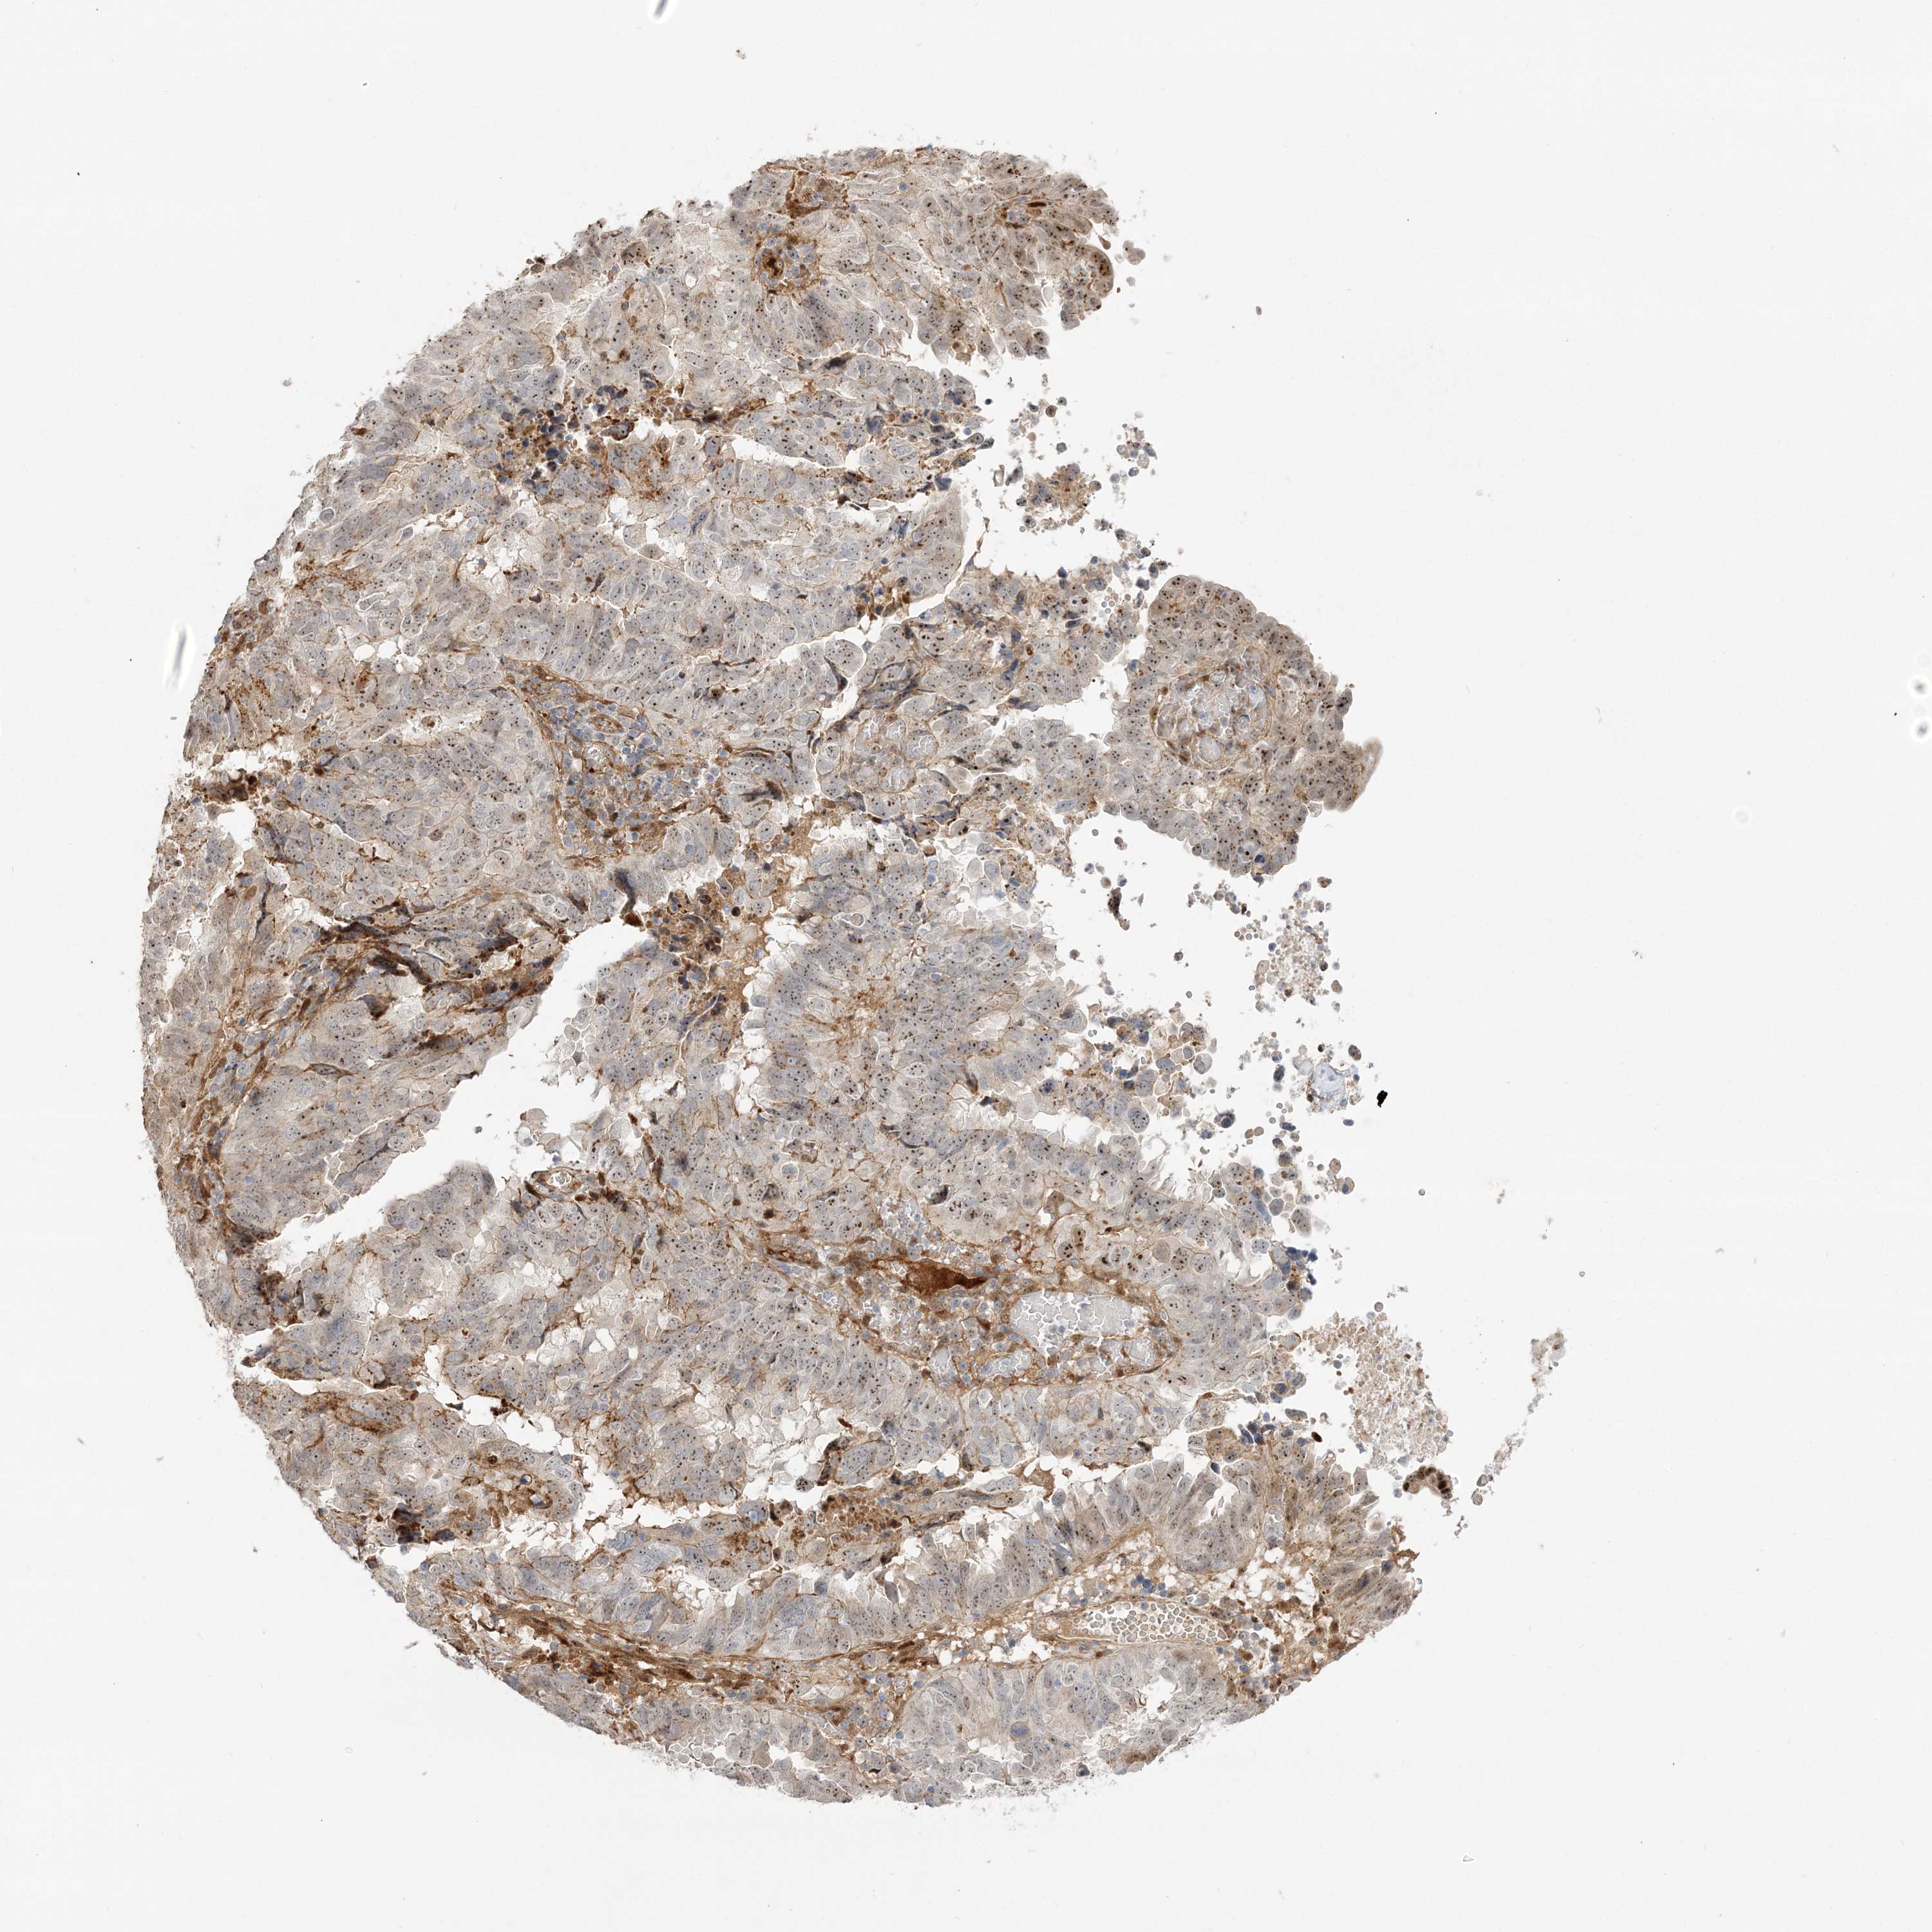

ENDOMETRIAL CANCER - Protein expressioni

A mouse-over function shows sample information and annotation data. Click on an image to view it in a full screen mode. Samples can be filtered based on level of antibody staining by selecting one or several of the following categories: high, medium, low and not detected. The assay and annotation is described here.

Note that samples used for immunohistochemistry by the Human Protein Atlas do not correspond to samples in the TCGA dataset.

Antibody stainingi

Antibody staining in the annotated cell types in the current human tissue is reported as not detected, low, medium, or high, based on conventional immunohistochemistry profiling in selected tissues. This score is based on the combination of the staining intensity and fraction of stained cells.

Each image is clickable and will lead to virtual microscopy that enables deeper exploration of all samples and also displays staining intensity scores, fraction scores and subcellular localization as well as patient and tissue information for each sample.

Antibody HPA036295

Antibody HPA036296

Staining

High

Medium

Low

Not detected

Intensity

Strong

Moderate

Weak

Negative

Quantity

>75%

75%-25%

<25%

None

Location

Nuclear

Cytoplasmic/membranous

Cytoplasmic/membranous,nuclear

Adenocarcinoma, NOS

Adenocarcinoma, metastatic, NOS